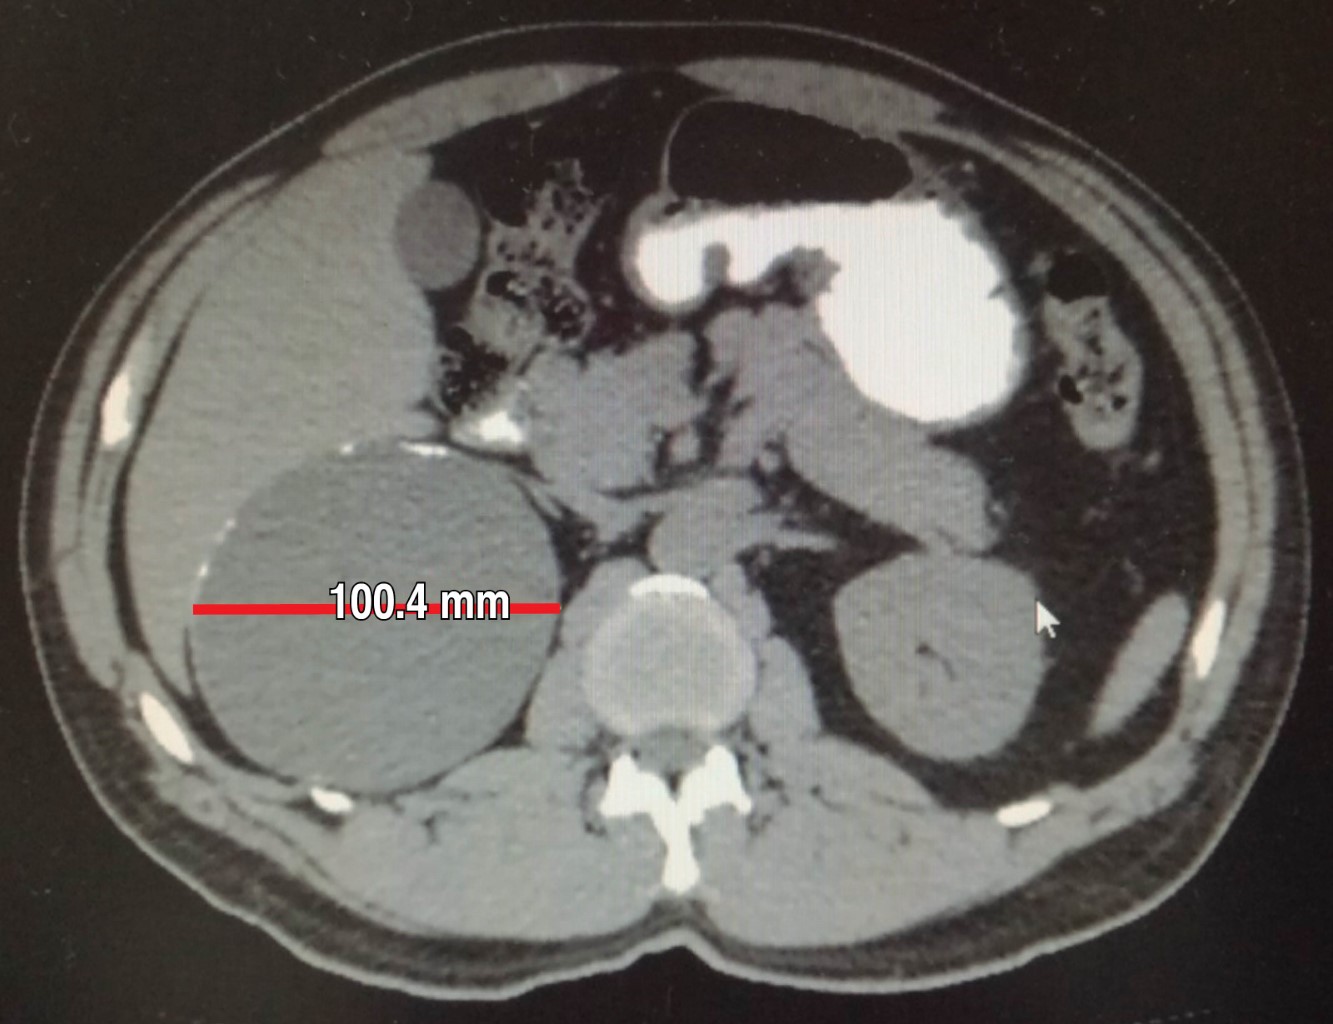

Biometría hemática, pruebas de función hepática, renales, TP y TPT de mayo de 2018 normales. No se realiza cortisol, aldosterona, catecolaminas urinarias ni metanefrinas. Tomografía de mayo reporta en glándula suprarrenal derecha imagen hipodensa con diámetros máximos de 101 mm, calcificaciones en su interior con efecto ocupativo y compresivo sobre las estructuras vecinas (Figuras 3, 4, 5 y 6). Completándose su valoración preoperatoria por medicina interna, se programa abordaje quirúrgico anterior abierto y bajo profilaxis antibiótica con ceftriaxona 2 g en dosis única, se realiza incisión subcostal derecha, destechamiento con electrocauterio de quiste suprarrenal derecho de 10 × 9 cm, con adherencias al hígado, contenido de aproximadamente 400 ml de líquido hialino y calcificaciones de alrededor de 20 × 40 mm en su interior. Se coloca drenaje abierto, penrose de ½" (19 mm) en espacio subfrénico ante la sospecha de hemorragia postoperatoria.

Figura 5

Figura 6